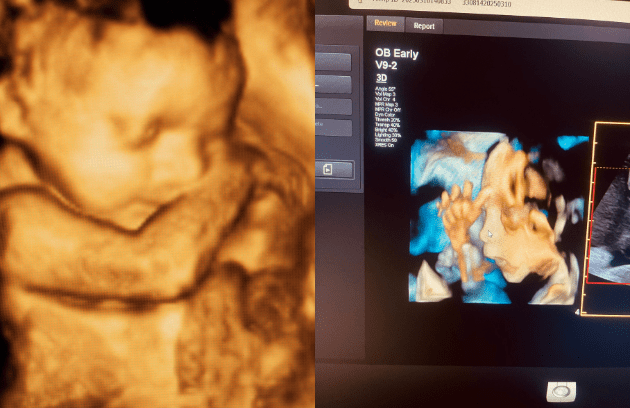

- Modern 4D ultrasound imaging

3D/4D Ultrasound